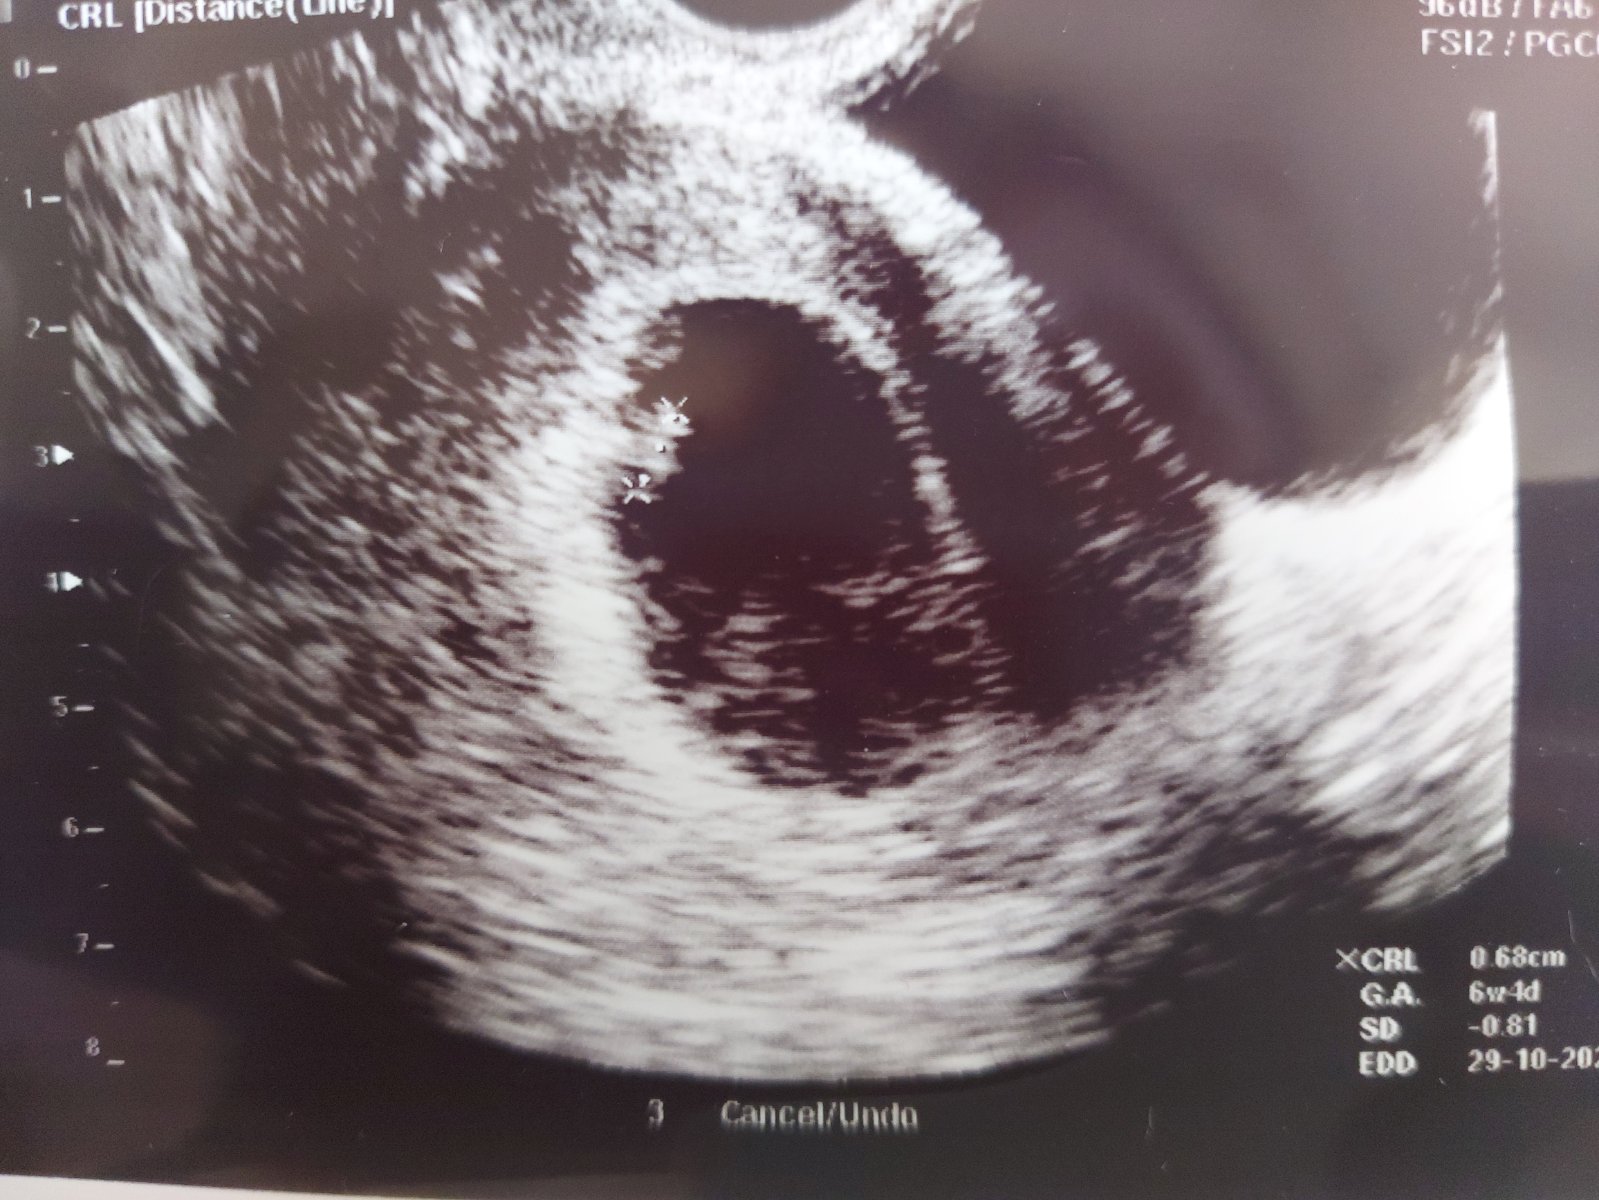

Prve sono, od ms je to 6tt+4 co aj pasuje podla sona🥰 lekarka hovorila ze vraj sa im malokedy stane ze prve IUI takto pekne vyjde, klop klop🙂 ale som zivym dokazom ze to vyjst moze a preto vam drzim vsetkym moc moc palce ❤